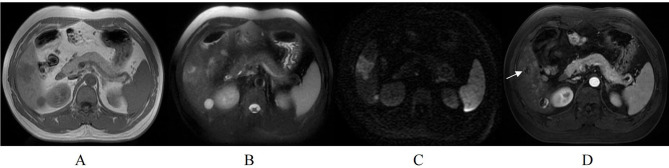

Results: The median RFS for the 134 patients was 45.7 months, with 41.8% of patients experiencing tumor recurrence after hepatectomy. Univariate Cox regression analysis identified hepatitis Be antigen (HBeAg) positivity, tumor size, tumor growth subtype, non-peripheral washout, nodule-in-nodule architecture, mosaic architecture, and intratumoral arteries as significant risk factors for RFS. Multivariate Cox regression analysis revealed that HBeAg positive, tumor growth subtype, non-peripheral washout, mosaic architecture, and internal arteries were independent prognostic factors for RFS in patients with solitary HCC without MVI. The nomogram based on these variables demonstrated good predictive accuracy, with concordance indices (C-index) of 0.740 and 0.701 in the training and validation cohorts, respectively. Additionally, patients in the high-risk group exhibited significantly lower RFS compared to those in the low-risk group.